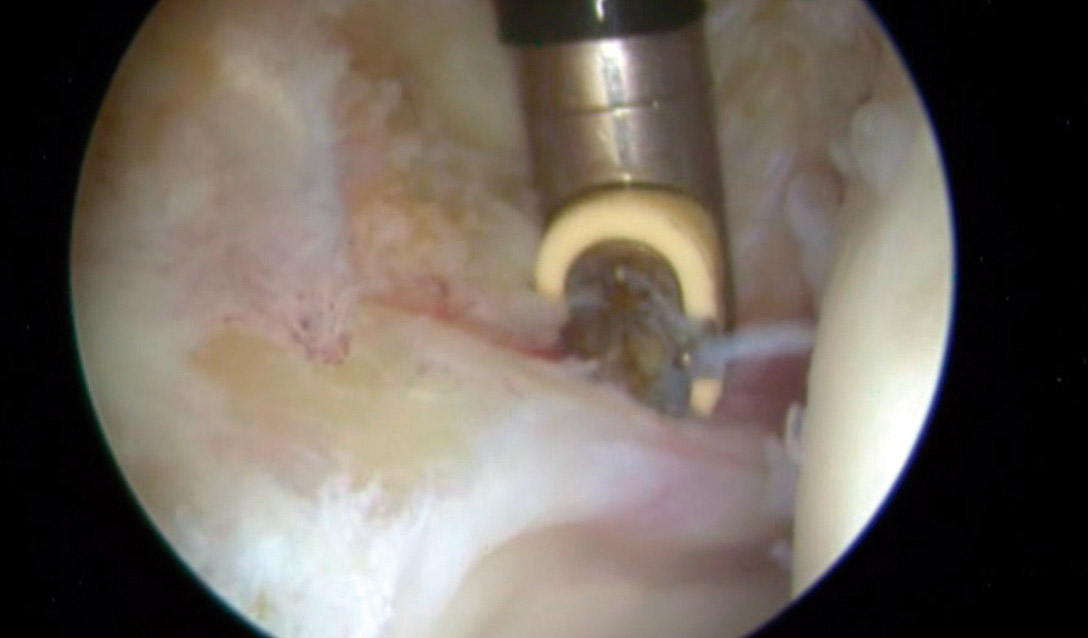

En la exploración artroscópica se observó un labrum hiperémico en la región anteroexterna, con un aumento del tejido sinovial adyacente al labrum. Se realizó una destrucción de dicho tejido mediante el uso de un vaporizador de radiofrecuencia, tal y como se observa en las Figuras 3 y 4. El complejo condrolabral se encontraba conservado y no requirió reanclaje.

En vista de su evolución, se decidió realizar una cirugía artroscópica de cadera derecha bajo la sospecha de AFA sin signos radiológicos. La imagen artroscópica mostraba un labrum hiperémico con una zona anterosuperior con rotura condrolabral y lesiones cartilaginosas acetabulares de tipo ALAD 1 con wave sign presente (Figura 7). Se realizó una sinovectomía local con vaporizador de radiofrecuencia y reanclaje labral mediante sutura.